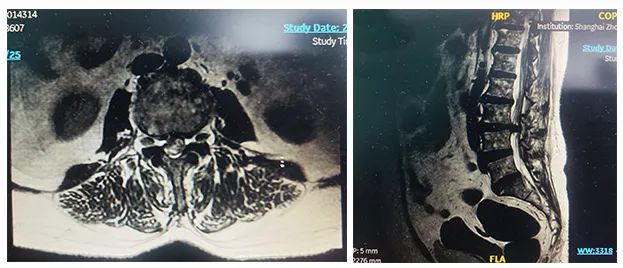

病例二

患者:女性,58歲

術(shù)式:腰骶椎椎體間融合術(shù)

患者一個(gè)月前因雙側(cè)下肢疼痛至醫(yī)院就診,診斷為腰椎間盤突出。患者自行至診所就診,予以推拿牽引術(shù),疼痛未明顯緩解,到醫(yī)院進(jìn)一步治療。影像診斷:L3-4椎間盤突出,椎管變窄(中央型)。

術(shù)前影像